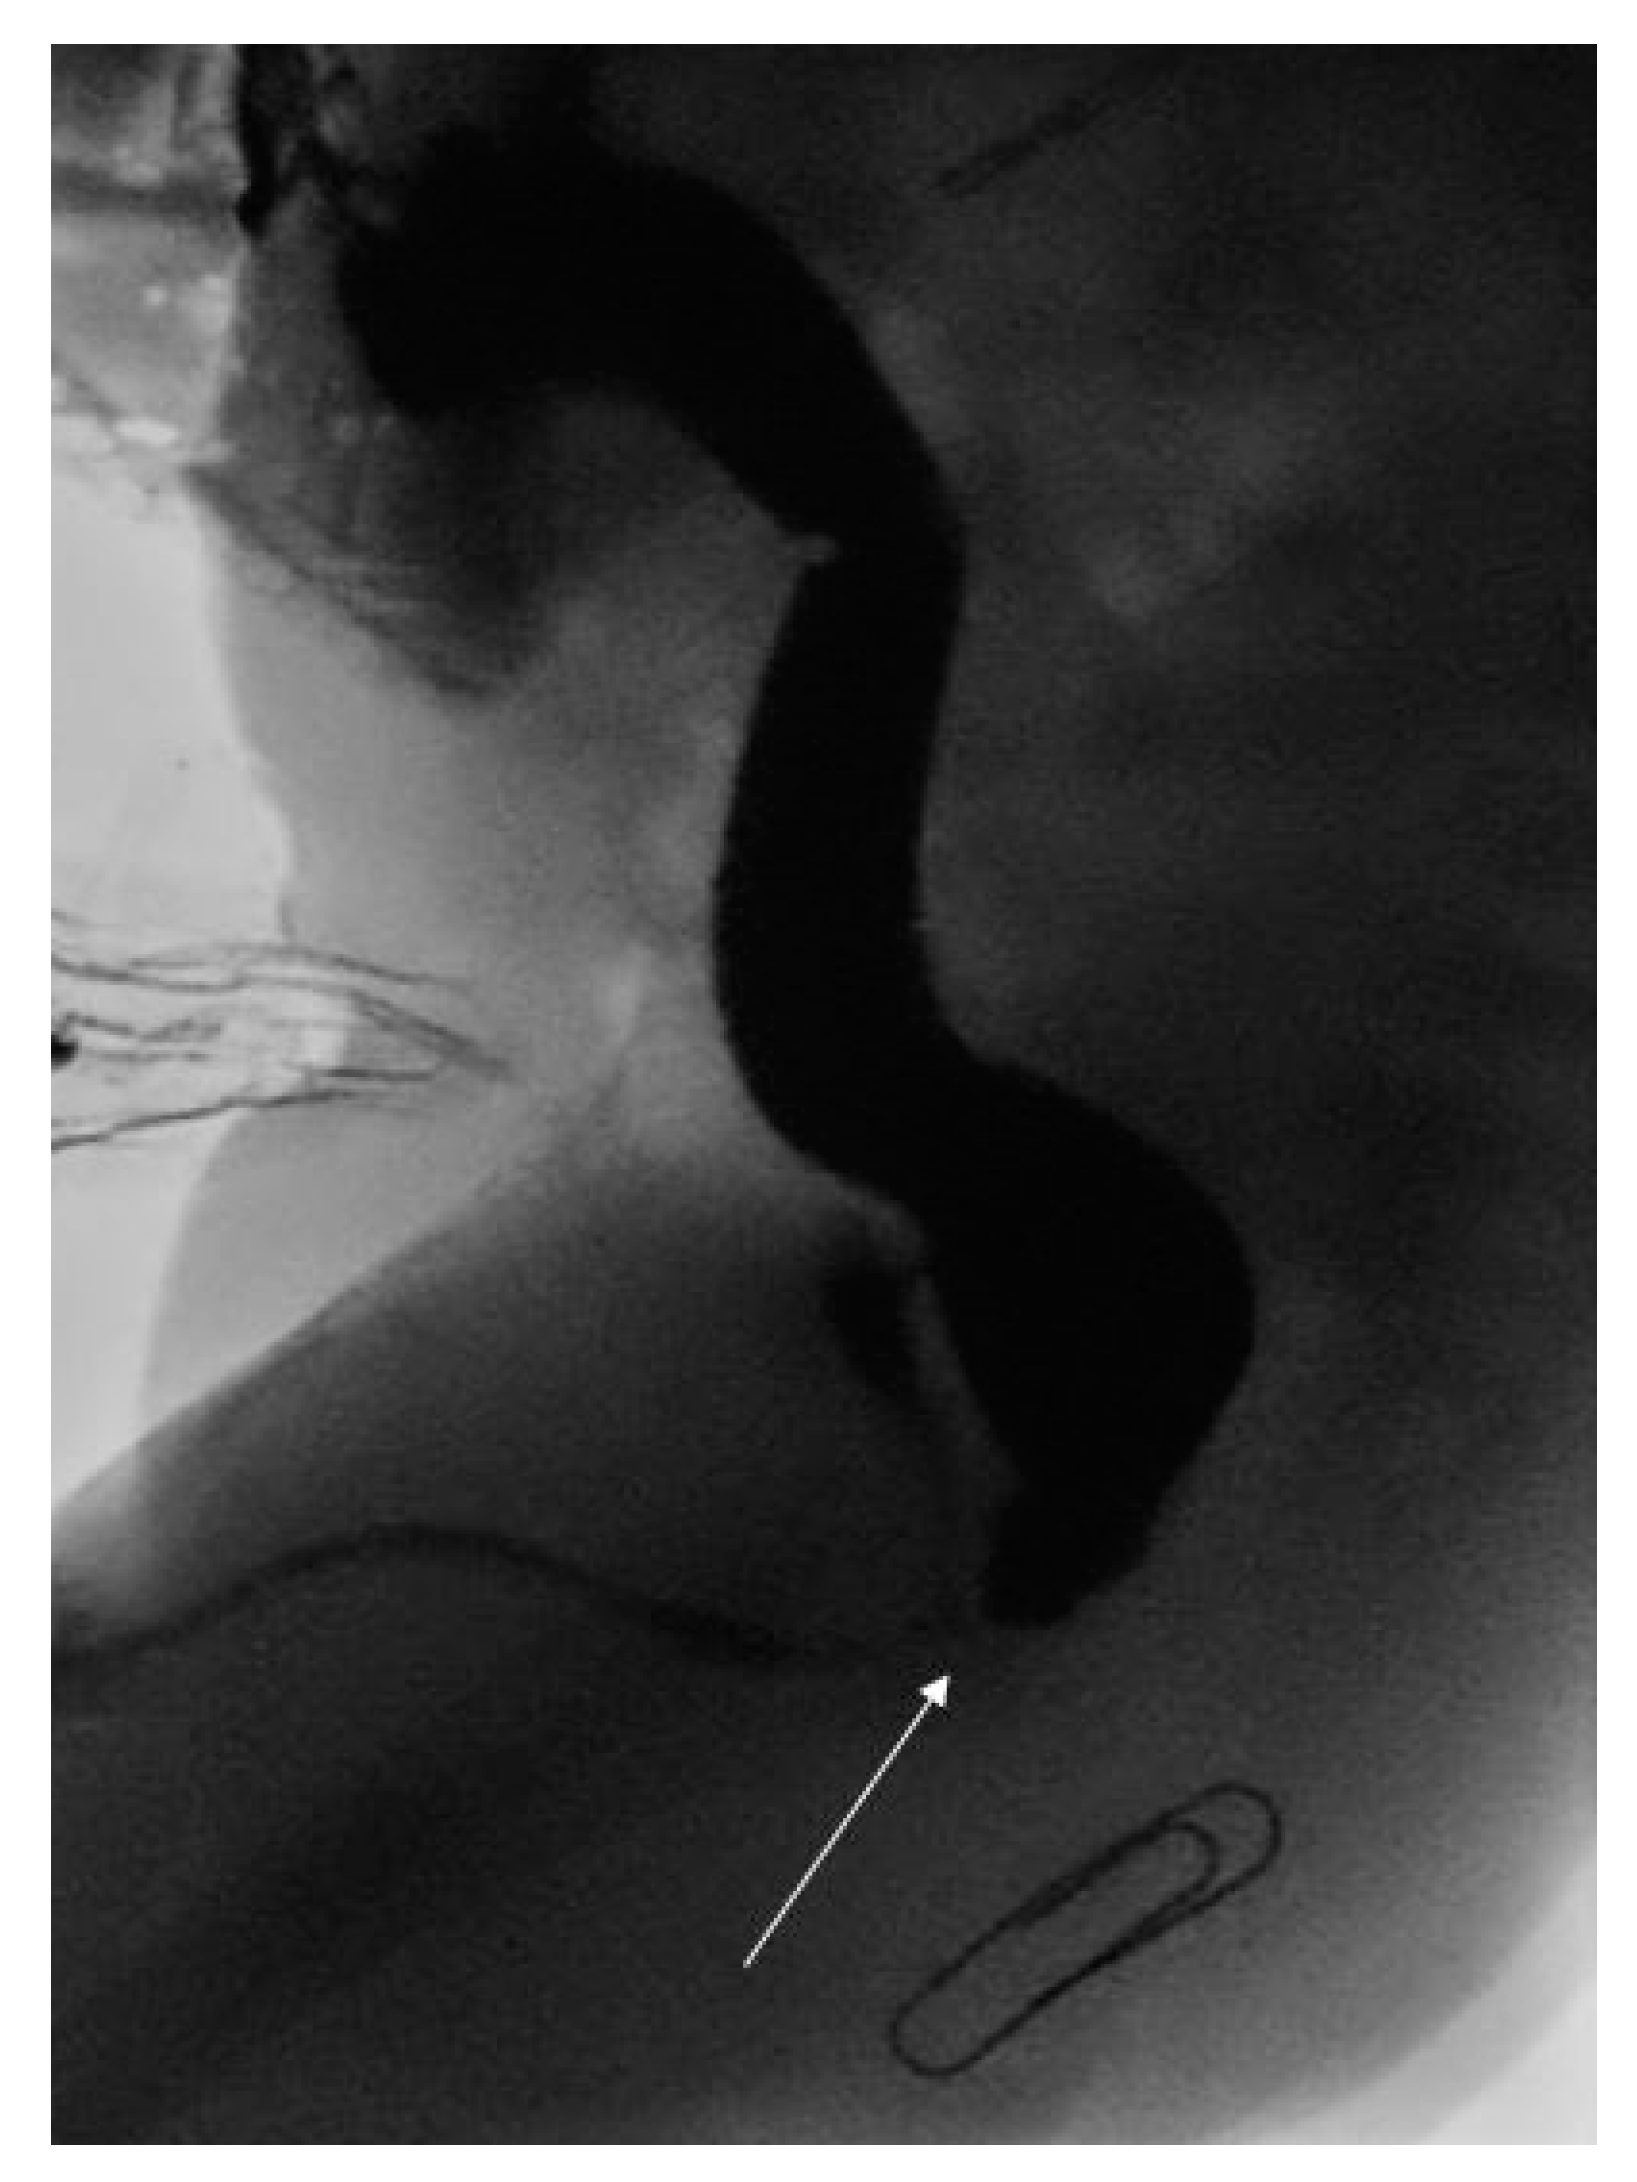

Following cardiac surgery, the child underwent a high pressure distal loopogram that confirmed a recto-bulbar ARM (see Figure 1). This was managed with a posterior sagital anorectoplasty (PSARP) on day 313 of life. Interestingly, due to the high position of the original stoma in the medial edge of the right transverse incision, the stoma had to be re-sited to avoid undue tension across the colo-anal anastamosis. He went on to have an uncomplicated post-operative recovery and remained well at one month follow up.

Figure 1.

High pressure distal loopogram demonstrating recto-bulbar fistula (white arrow) and expected position of neo-anus (paper clip).